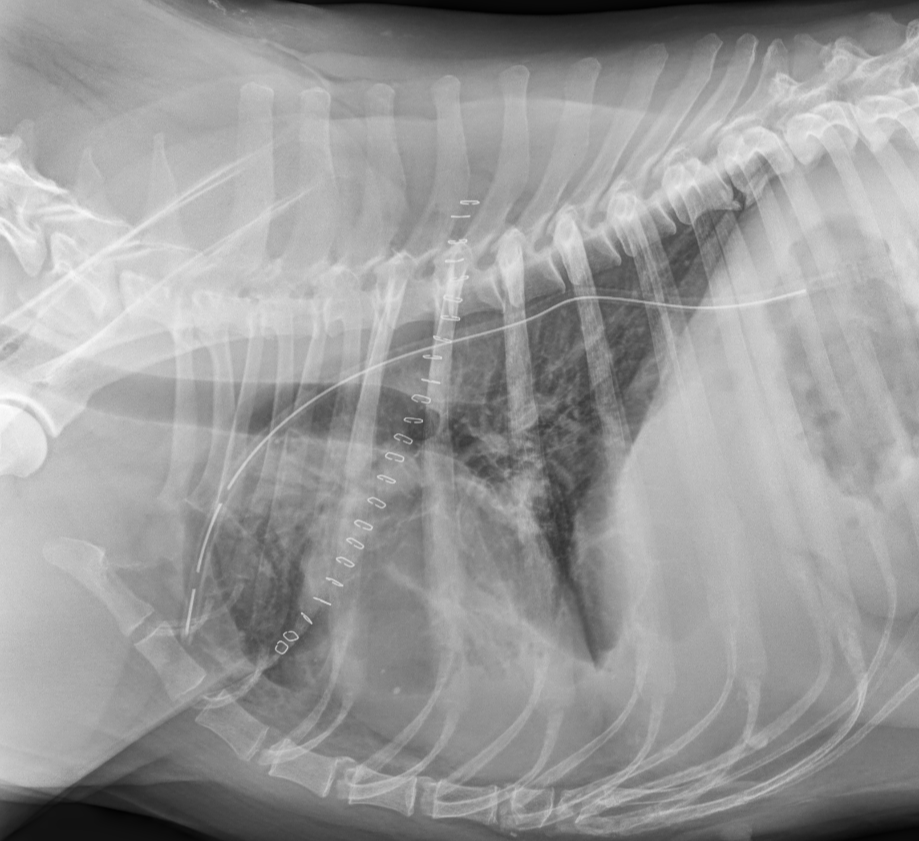

Hashtag, eine große Mischlingshündin, zeigt auf dem Röntgenbild ihres Haustierarztes eine große Masse im Thorax. Nach dem Staging mittels CT und Biopsie bei uns stand fest, eine Operation ist sinnvoll. Aus dem offenen Brustkorb wurde Hashtag ein mandarinengroßer Tumor entfernt. Die Narkose unter künstlicher Beatmung verlief problemlos. Nach Entfernung und dem Brustkorbverschluss unter Einlegen einer Thoraxdrainge, erholte sich Hashtag sehr schnell und wurde nach einigen Tagen entlassen.